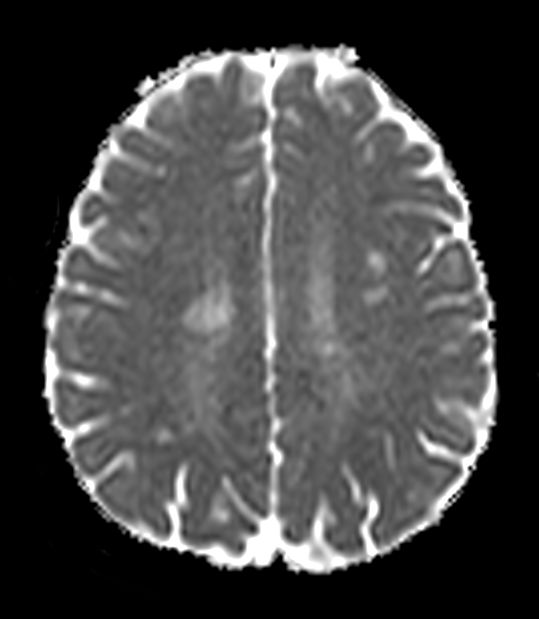

Brain - White matter lesions

Fast and high quality brain imaging for a patient with white matter lesions. AI based SmartSpeed is utlized to shorten scan time without compromise in image quality. Advanced 3D TSE imaging technique are used to acquire high resolution data in multiple directions in only one single scan.

Axial DWI b1000 (ADC)